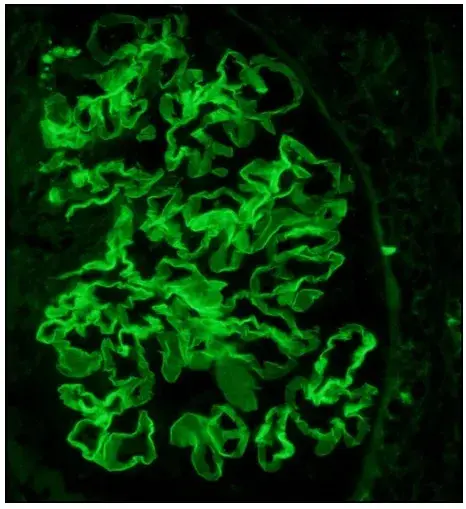

A imunofluorescência mostra marcação linear de IgG na MBG (anticorpo anti-IgG; 400×).

A imunofluorescência demonstrou padrão de deposição linear de IgG (policlonal), deposição na membrana basal glomerular (MBG), sem depósitos na microscopia eletrônica.